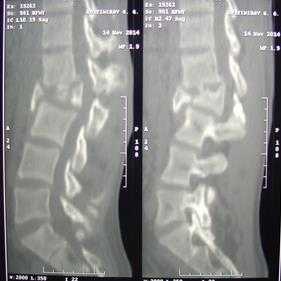

Результаты исследования. В результате одноэтапного хирургического лечения ПСМТ передний костный блок сформировался в течение 8±1,5 месяца после операции (рис. 1).

Рис. 1. Одноэтапное лечение ПСМТ пациента Г., 20 лет: рентгенограммы (вверху) и КТ-сканы (внизу). Взрывной, осложненный перелом L2. А - до лечения. Кифотическая деформация грудопоясничного отдела позвоночника со стенозом позвоночного канала. Легкий нижний парапарез (тип D по ASIA/ISNSCI). Болевой синдром. Б - после лечения. Спондилосинтез L1-L3, VCR L2 с декомпрессией невральных структур. Передний спондилодез на уровне L1-L3 из заднего доступа с коррекцией деформации